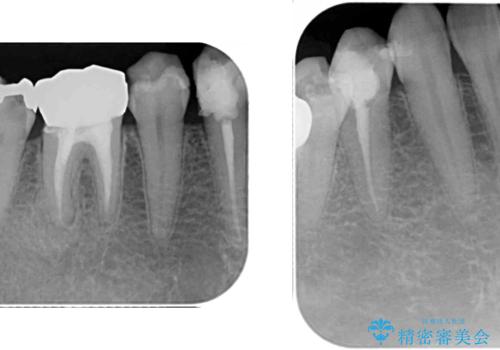

他にも、奥歯の銀歯の下にもむし歯が多くあり、痛みが生じていたため、根管治療などを行った上で、オールセラミッククラウンにて補綴治療することとしました。

前歯の裏側の接着面は、隙間ができていたことにより、汚れがたまるだけでなく、むし歯にもなっていました。

我々としては、治療により状態が悪化することだけは避けたいと考えているため、歯全体を覆うクラウンにすることで、より長持ちする治療を提供いたしました。